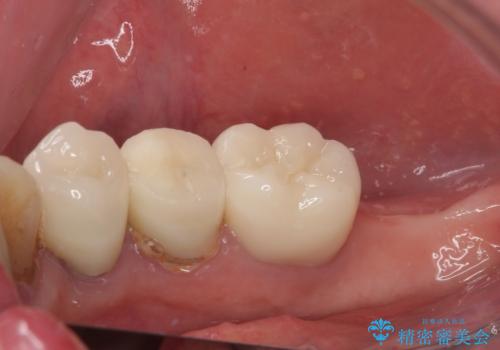

破折してしまった奥歯 抜歯即時埋入で短期間インプラント治療

- 奥歯に装着していたクラウンが外れてしまったとのことで来院された患者様です。

診察したところ、歯根に破折線が確認され抜歯が必要な状態でした。

歯肉や歯槽骨の状態は良好であったため、抜歯即時埋入インプラントによる補綴治療を行うこととしました。

抜歯、インプラント埋入、仮歯の装着を1度に行うことができ、治療終了までわずか3か月で終えることができました。